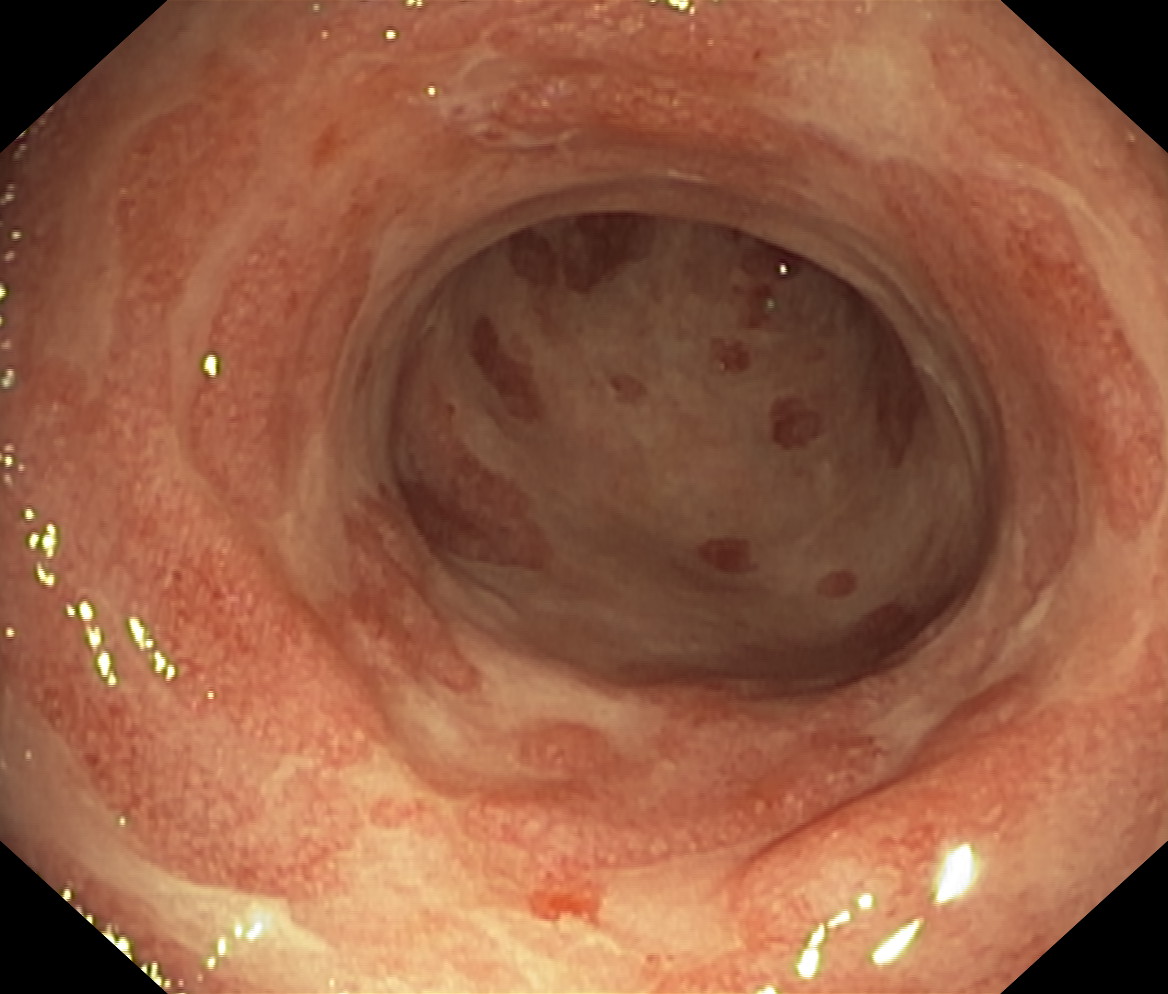

Zapalenie wrzodziejące...

Zapalenie wrzodziejące jelita grubego